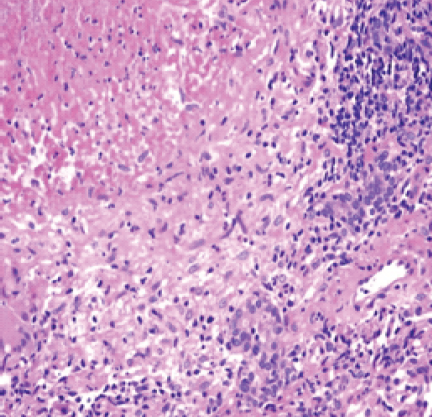

The cartridge-based nucleic acid amplification test (CBNAAT) was positive for Mycobacterium tuberculosis. Ziehl–Neelsen stain demonstrated acid-fast bacilli. Histopathology showed epithelioid granulomas with Langhans giant cells (Fig. 4) and caseous necrosis, diagnostic of TB osteomyelitis.

Figure 4: Tuberculous granuloma with central necrosis, epitheloid cells.